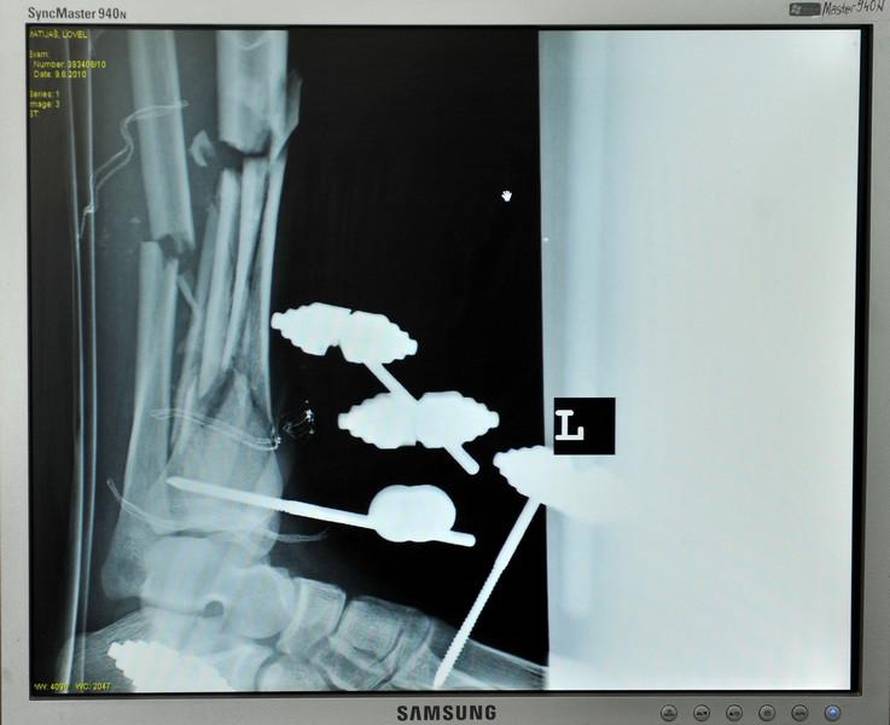

U Hrvatskoj je u 2009. poginulo 96 motociklista, a ozlijeđeno ih je 3207. Motoristi su u bolnici vidjeli kako izgledaju žrtve teških prometnih nesreća